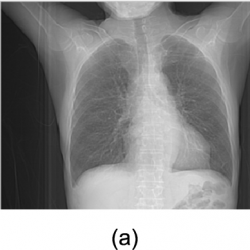

Mobile and digital media are getting more and more popular on Internet and cloud services. In social networks, many multi-media such as images, videos, and audios are produced by different aspects of the human activities. Moreover, telemedicine applies telecommunication and information technology to offer clinical health care from a distance. In critical care and emergency situations, health informatics, medical, and imaging data are transmitted from doctors and healthcare professionals to discuss patient issues. Therefore, E-Healthcare data management plays a crucial role in modern hospitals. Over Internet and cloud services, digitized healthcare systems have provided easy access, viewing and sharing of digitized medical images to patients, doctors, medical professionals, health care providers, and institutes of medicine. Medical images may provide for teleconferences among clinicians, interdisciplinary exchanges between radiologists for consultative purposes, and distant learning of medical personnel. For illegal purposes used for insurance, for example, digital medical malignant nodule images may be modified on lung parenchyma in chest CT scan images. Therefore, data hiding schemes (Wang